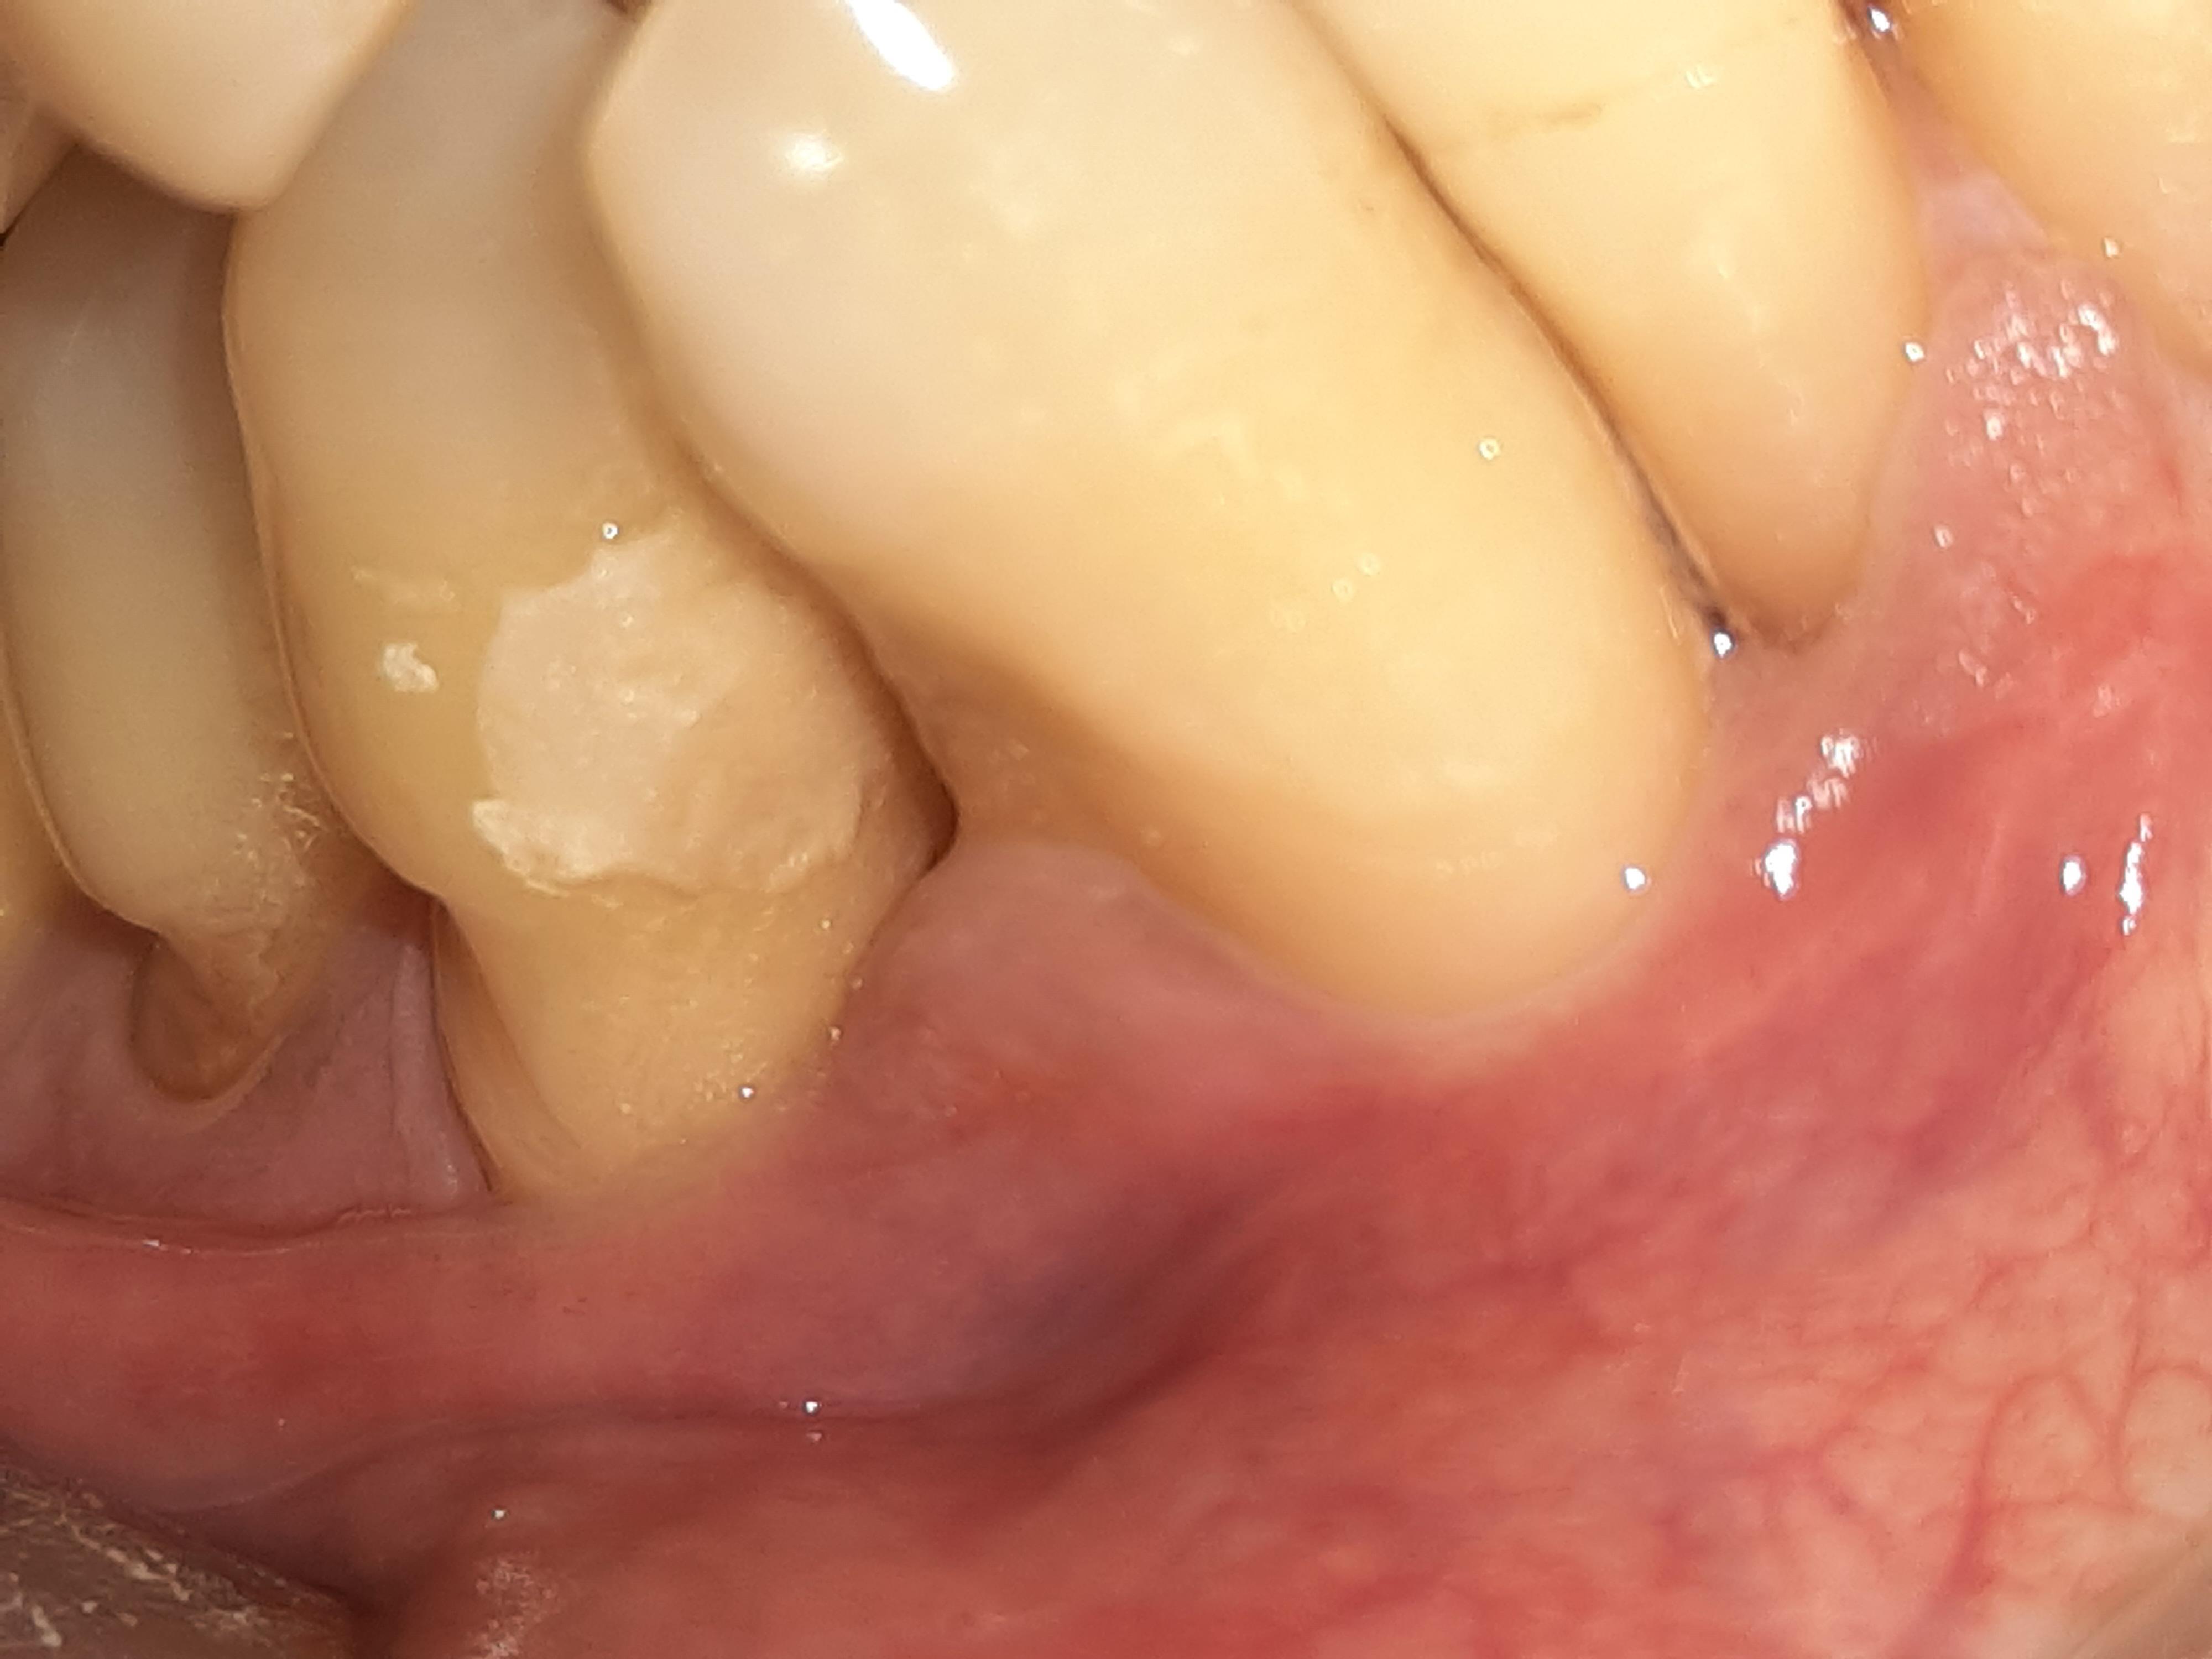

Root caries is frequently undiagnosed in a busy general dental practice . If you look around you will find many cases if root carries . As would be obvious these will be senior citizens who have experienced gum recession .

Wheneever you see a patient with gum recession loo out for root caries.

After filling / Note : Final polishing is pending